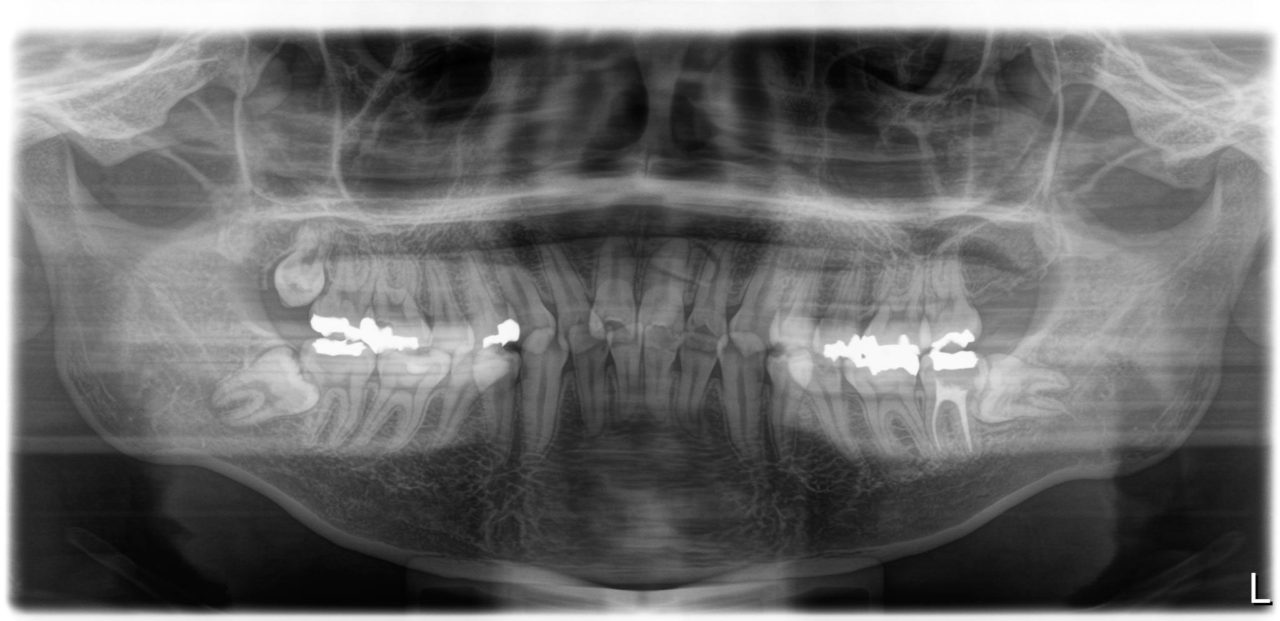

初診 パノラマレントゲン

| 備考 | 左上中切歯の根尖性歯周炎で来院されました。根っこの先に過剰歯があり、左上中切歯の神経は死んでいました。根管治療後、歯列不正を改善のために矯正治療を提案しました。小臼歯4本抜歯を伴うものですが、噛み合わせが良くなるだけでなく、口元もかなりすっきりし、審美を得られる可能性があることを説明をしたところ、快く了承をしていただけました。失活歯で予後不良の左下第2大臼歯も抜歯し、親知らずを利用しました。すべての治療期間は23か月かかりましたが、今後の人生が楽しみになる顔貌の良化を遂げたと考えます。ご本人にも非常に喜んでいただけました。 |